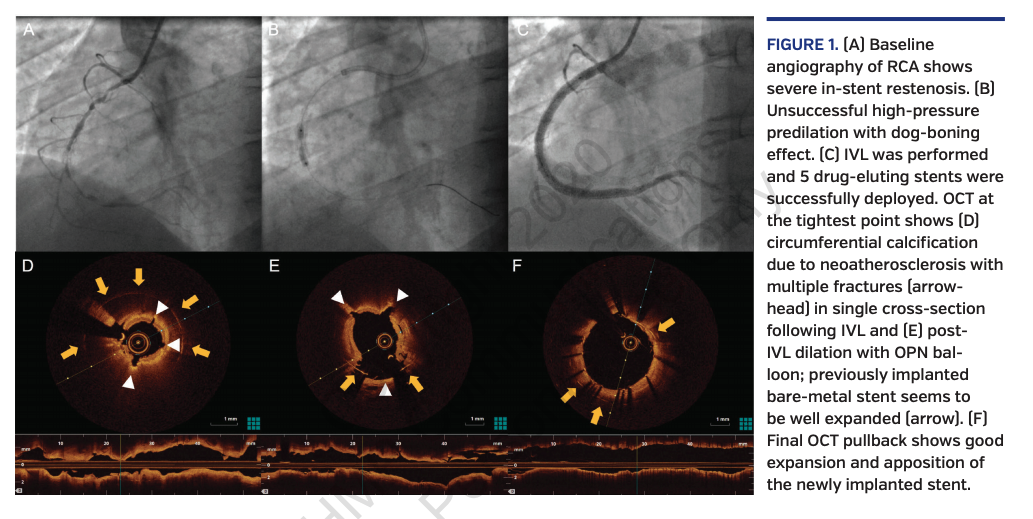

A 38-year-old male underwent successful recanalization of a chronic total occlusion (CTO) in a bare-metal stented segment of the mid right coronary artery (RCA) via retrograde approach. However, the in-stent restenotic lesion was undilatable despite pressure up to 35 atm with non-compliant (NC) OPN balloons (SIS Medical AG). The patient was discharged with plans for a future attempt. Six months later, coronary angiography revealed patency of the RCA with residual severe in-stent restenosis. Predilation with a 2.5 x 15 mm OPN NC balloon up to 35 atm confirmed the undilatable restenotic lesion with dog-boning effect. Therefore, coronary lithoplasty with the Coronary Rx Intravascular Lithotripsy System (Shockwave Medical) was performed with a 2.5 x 12 mm balloon, delivering 8 series of lithotripsy. Subsequent dilation with a 3.0 x 15 mm OPN NC balloon at 35 atm was sufficiently effective and 5 overlapping drug-eluting stents were successfully deployed from the posterior-lateral ramus to ostial RCA. Coronary angiography and optical coherence tomography with the Ilumien Therapy Guidance System (St. Jude Medical) findings are shown in Figure 1.

Coronary lithoplasty is a promising technique that can overcome issues regarding the treatment of undilatable, heavily calcified, de novo and in-stent restenotic lesions, allowing plaque modification and successful stent deployment as demonstrated by intravascular imaging.